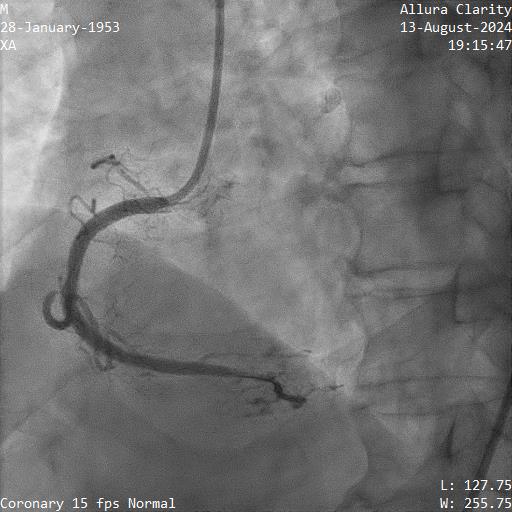

4. Proximal RCA was diffuse disease 70-80%, mid to distal RCA was a CTO. Ipsilateral CC from marginal to PDA

Right femoral and right radial arteries were punctured. A 7Fr EBU 3.5 guiding catheter (GC) was used to engage LMT. A 7Fr JR 4 GC was used for RCA CTO PCI. For antegrade preparation, a wire was delivered into right marginal artery. For antegrade proximal cap puncture, a Finecross microcatheter (MC) and Fielder XTR was used to wire into mid RCA CTO, but XTR fail to advance further. For retrograde approach, a CorsairPro ES (150 cm) MC, SION and SUOH 03 wire were used for LAD septal wiring but failed. A Sion Black with 90 degree tip successfully negotiate the collateral and entered PDA. The distal cap was hard to puncture. UB3 was used to puncture the distal cap and managed to cross and externalized into antegrade GC. Attempt was made to advance retrograde MC but failed at the point of PDA/PLV bifurcation.

Next plan was using retrograde UB3 to tip in antegrade MC successfully. However, the antegrade MC crossed the CTO body but failed cross PDA despite anchoring balloon at marginal artery. Next, switched to antegrade, escalated the antegrade wire to GAIA Next2 and using retrograde wire as a marker to facilitate antegrade wiring. Fortunately, the GAIA Next 2 managed to entered PLV. IVUS confirmed wire in true lumen after predilatation. The PDA was wired using CRUSADE MC to keep wire access for PDA and PLV.Distal RCA-PDA stented with everolimus eluting stent (EES) 2.5x32mm, mid RCA EES 3.5x32mm, and ostial RCA EES 4.0x24mm, post dilated NC 3.0x15mm, and 4.0x15mm balloon.

Next plan was using retrograde UB3 to tip in antegrade MC successfully. However, the antegrade MC crossed the CTO body but failed cross PDA despite anchoring balloon at marginal artery. Next, switched to antegrade, escalated the antegrade wire to GAIA Next2 and using retrograde wire as a marker to facilitate antegrade wiring. Fortunately, the GAIA Next 2 managed to entered PLV. IVUS confirmed wire in true lumen after predilatation. The PDA was wired using CRUSADE MC to keep wire access for PDA and PLV.Distal RCA-PDA stented with everolimus eluting stent (EES) 2.5x32mm, mid RCA EES 3.5x32mm, and ostial RCA EES 4.0x24mm, post dilated NC 3.0x15mm, and 4.0x15mm balloon.